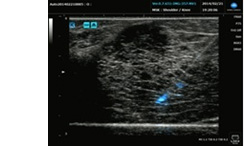

超音波プローブに独自開発した音響材料を用いて高感度化と広帯域化の両立を実現するとともに、高次高調波を用いた「広帯域ハーモニックイメージング」によって従来よりも多くの信号を画像化に利用できるようにしました。さらにX線画像診断分野で培った画像処理技術「HS処理※2」を応用し、組織の描出力を飛躍的に高め、クラス最高レベル※1の分解能を実現させました。これにより、太さ数十~数百ミクロン程度の筋束や神経束の繊維構造まで鮮明に見える高画質な画像が提供でき、医師の診断を強力にバックアップします。

神経ブロック注射や中心静脈穿刺でカテーテルを挿入する際、針が目的部位に到達しているかどうかを超音波ガイド下で確認することがあります。このとき針が皮膚表面から急な角度で刺された場合、従来の方式では針の検出が困難でした。本製品は、独自のアルゴリズムで針の位置を算出し画面上で光らせて針視認性を向上させる「穿刺針強調表示」によってこの問題を解決し、より安心安全な診断をサポートします。

プローブ内部に使われる音響材料を独自開発し音響伝搬ロスの低減や広帯域化が可能になりました。また、広帯域送受信画像エンジンと画像処理を組合せ、高次高調波を用いた「広帯域ハーモニックイメージング」技術を開発し、より高い分解能を実現しました。さらに、X線画像診断システムで培った画像処理技術「HS処理※2」を応用し、体内組織の描出力を飛躍的に高め、高精細で診断価値の高い画像の提供を可能にしました。

3.針の進入角度を選ばない穿刺針強調表示

画像処理を用いた穿刺針強調アルゴリズムにより、超音波信号の反射強度に依存せず、穿刺針を確実に捉え視覚的に強調して見せる機能を搭載しました。In-plane法の高角度な穿刺や、Out-plane法穿刺における針視認性を向上し、より安心で安全な穿刺治療をサポートします。